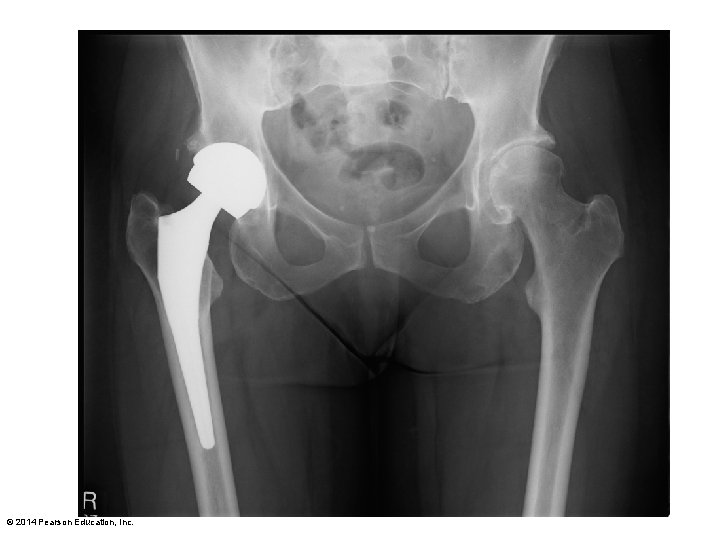

Figure 8. 12 The hip joint. Acetabular labrum Coxal (hip) bone Articular cartilage Acetabular labrum Ligament of the head of the femur (ligamentum teres) Synovial membrane Femur Ligament of the head of the femur (ligamentum teres) Head of femur Articular capsule (cut) Synovial cavity Articular capsule Frontal section through the right hip joint Photo of the interior of the hip joint, lateral view Iliofemoral ligament Ischium Ischiofemoral ligament Greater trochanter of femur Posterior view of right hip joint, capsule in place © 2014 Pearson Education, Inc. Anterior inferior iliac spine Iliofemoral ligament Pubofemoral ligament Greater trochanter Anterior view of right hip joint, capsule in place

Figure 8. 12 b The hip joint. Acetabular labrum Synovial membrane Ligament of the head of the femur (ligamentum teres) Head of femur Articular capsule (cut) Photo of the interior of the hip joint, lateral view © 2014 Pearson Education, Inc.